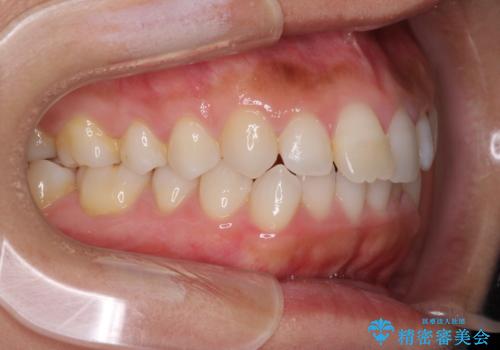

前歯の叢生を治したい インビザラインによる矯正治療

- 上下の前歯のデコボコと奥歯の反対咬合を気にして来院された患者様です。

インビザラインを用い、上下顎ともにIPR(歯と歯の間を削る)により叢生を改善することとしました。

奥歯の反対咬合は、骨格に由来するものであるため、改善できるところまで改善していくこととしました。

治療を長期化させたくないとのご要望があったので、左下の90度捻転した歯は、捻転した状態のゴールとしました。

反対咬合を改善したことで、歯ぎしりしたときの引っかかる感じがなくなり、奥歯への負担を大きく軽減することができました。